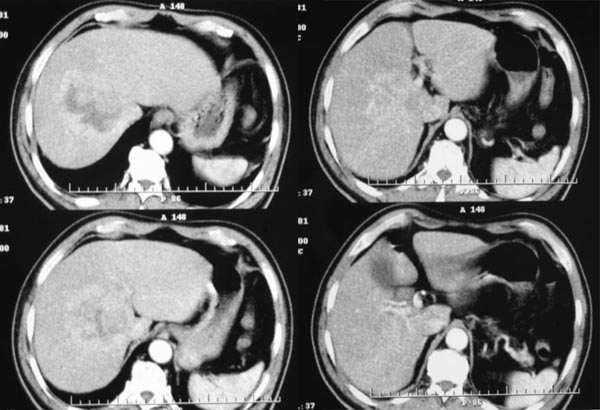

延时期

从动脉期到延时期可见病灶内有星芒样不强化裂隙,考虑fnh。鉴别:1血管瘤,逐渐强化,延时期造影剂填充呈高密度。2肝癌,早进早出。

早期强化不是很明显,血供不是很丰富,与肝实质相比还是呈快进快出的特点,中心裂隙样坏死,支持原发性肝癌。

平扫:团块状低密度灶,动脉期:边缘环形强化,门脉期:增强逐步向中心推进,实质期:强化进一步明显,中心呈裂隙样无强化影。所以首先考虑血管瘤